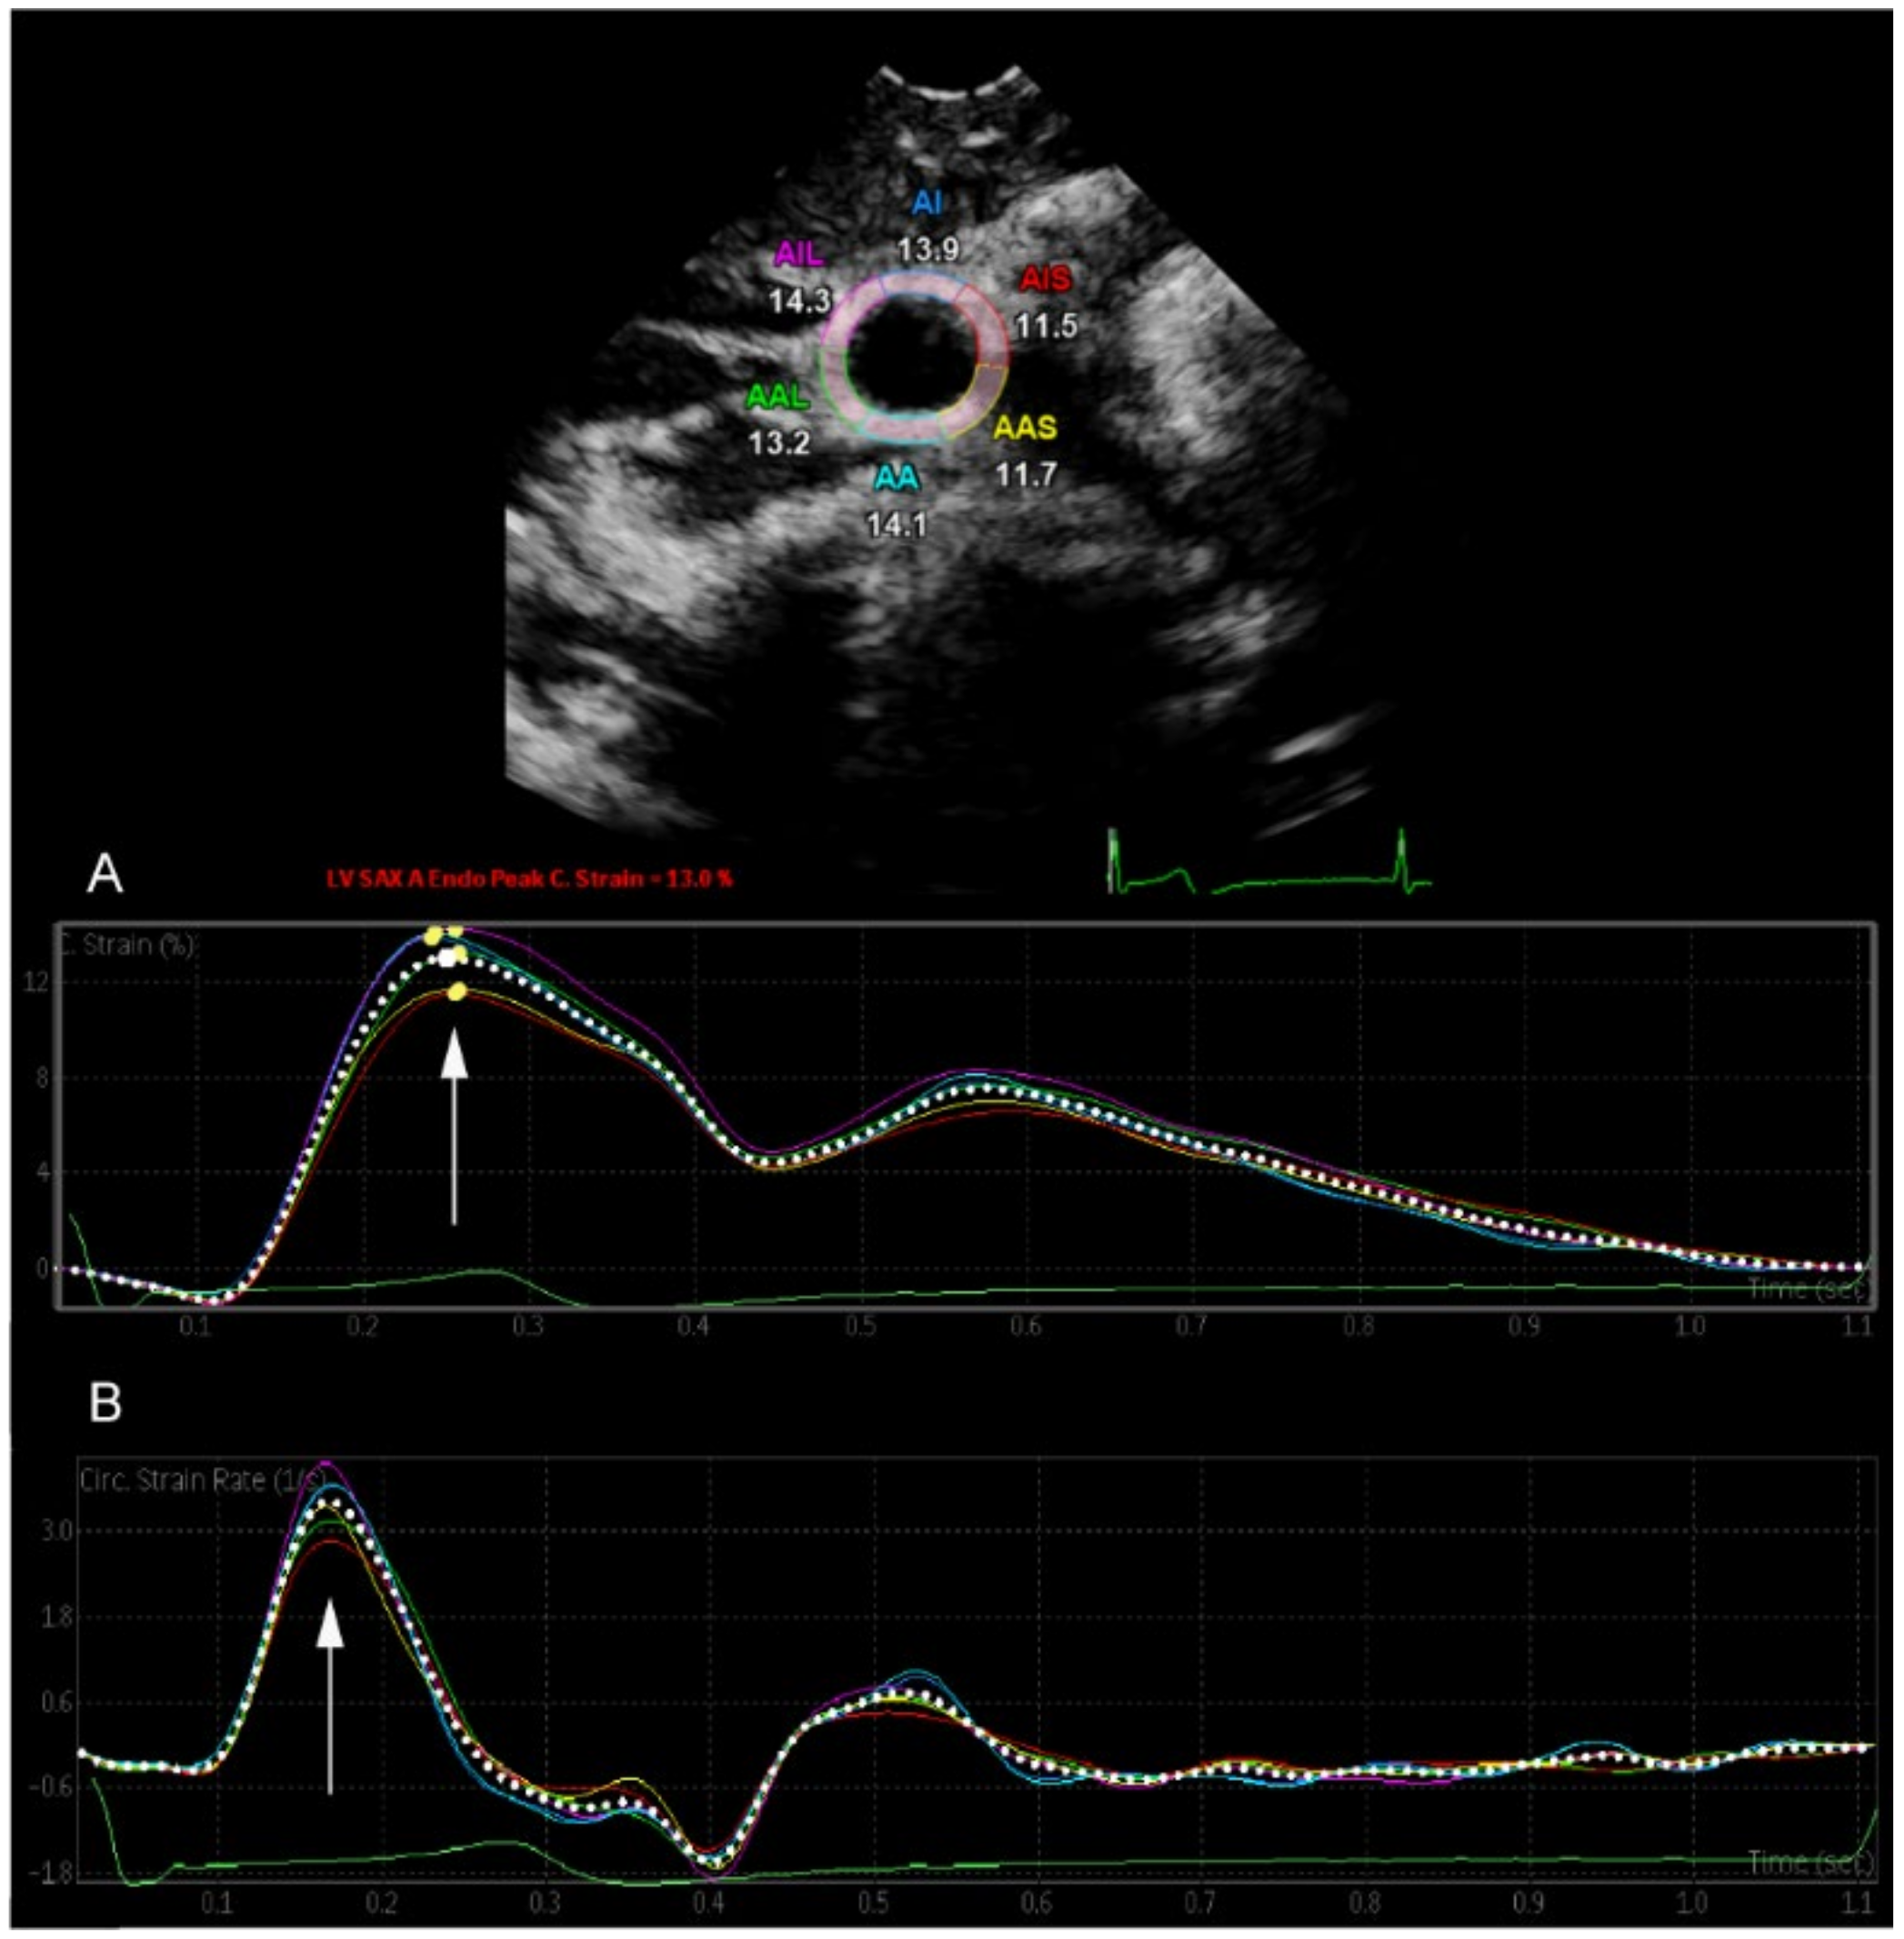

An iE33 xMatrix and an Epiq 7G ultrasound machine (Philips, Amsterdam, The Netherlands) were used for examination. Both common carotid arteries (CCA) were recorded in short-axis view just below carotid bifurcation with a 3–8 MHz sector array transducer. During the entire examination period, study participants were in supine position, and the neck was extended to a 45° angle and turned to the opposite side of examination. Three consecutive loops were acquired under constant three-lead ECG tracking. Recorded clips were then transferred to a separate workstation (QLAB cardiovascular ultrasound quantification software, version 11.1, Philips, Amsterdam, The Netherlands). Peak circumferential strain (CS, %) and peak strain rate (SR, s−1) of both CCAs were measured semi-automatically through the software’s function “SAX-A”. The vascular region of interest was manually adjusted. Speckles of the vessel wall were then two-dimensionally tracked, as visualized in Figure 1. A masked investigator analyzed the recorded loops three consecutive times, and an average was then calculated. Arterial distensibility (mmHg−1 × 10−3) was defined as

Figure 1.

Two-dimensional speckle tracking of the common carotid artery. The arrow indicates (A) peak circumferential strain (CS, %) and (B) peak strain rate (SR, s−1).